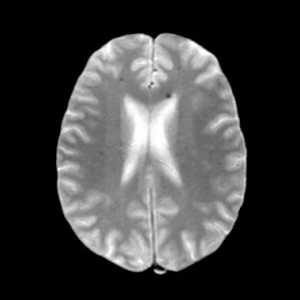

![множественные каверномы]()

На МР-изображении в режиме градиентного эхо визуализируются множественные двусторонние мелкие точечные и округлые очаги низкой интенсивности в перивентрикулярном и субкортикальном белом веществе. Самый крупный очаг визуализируется в перивентрикулярном белом веществе лобной доли кпереди от переднего (лобного) рога левого бокового желудочка около колена мозолистого тела. Кпереди и кзади от него видны множественные очаги более мелкого размера.